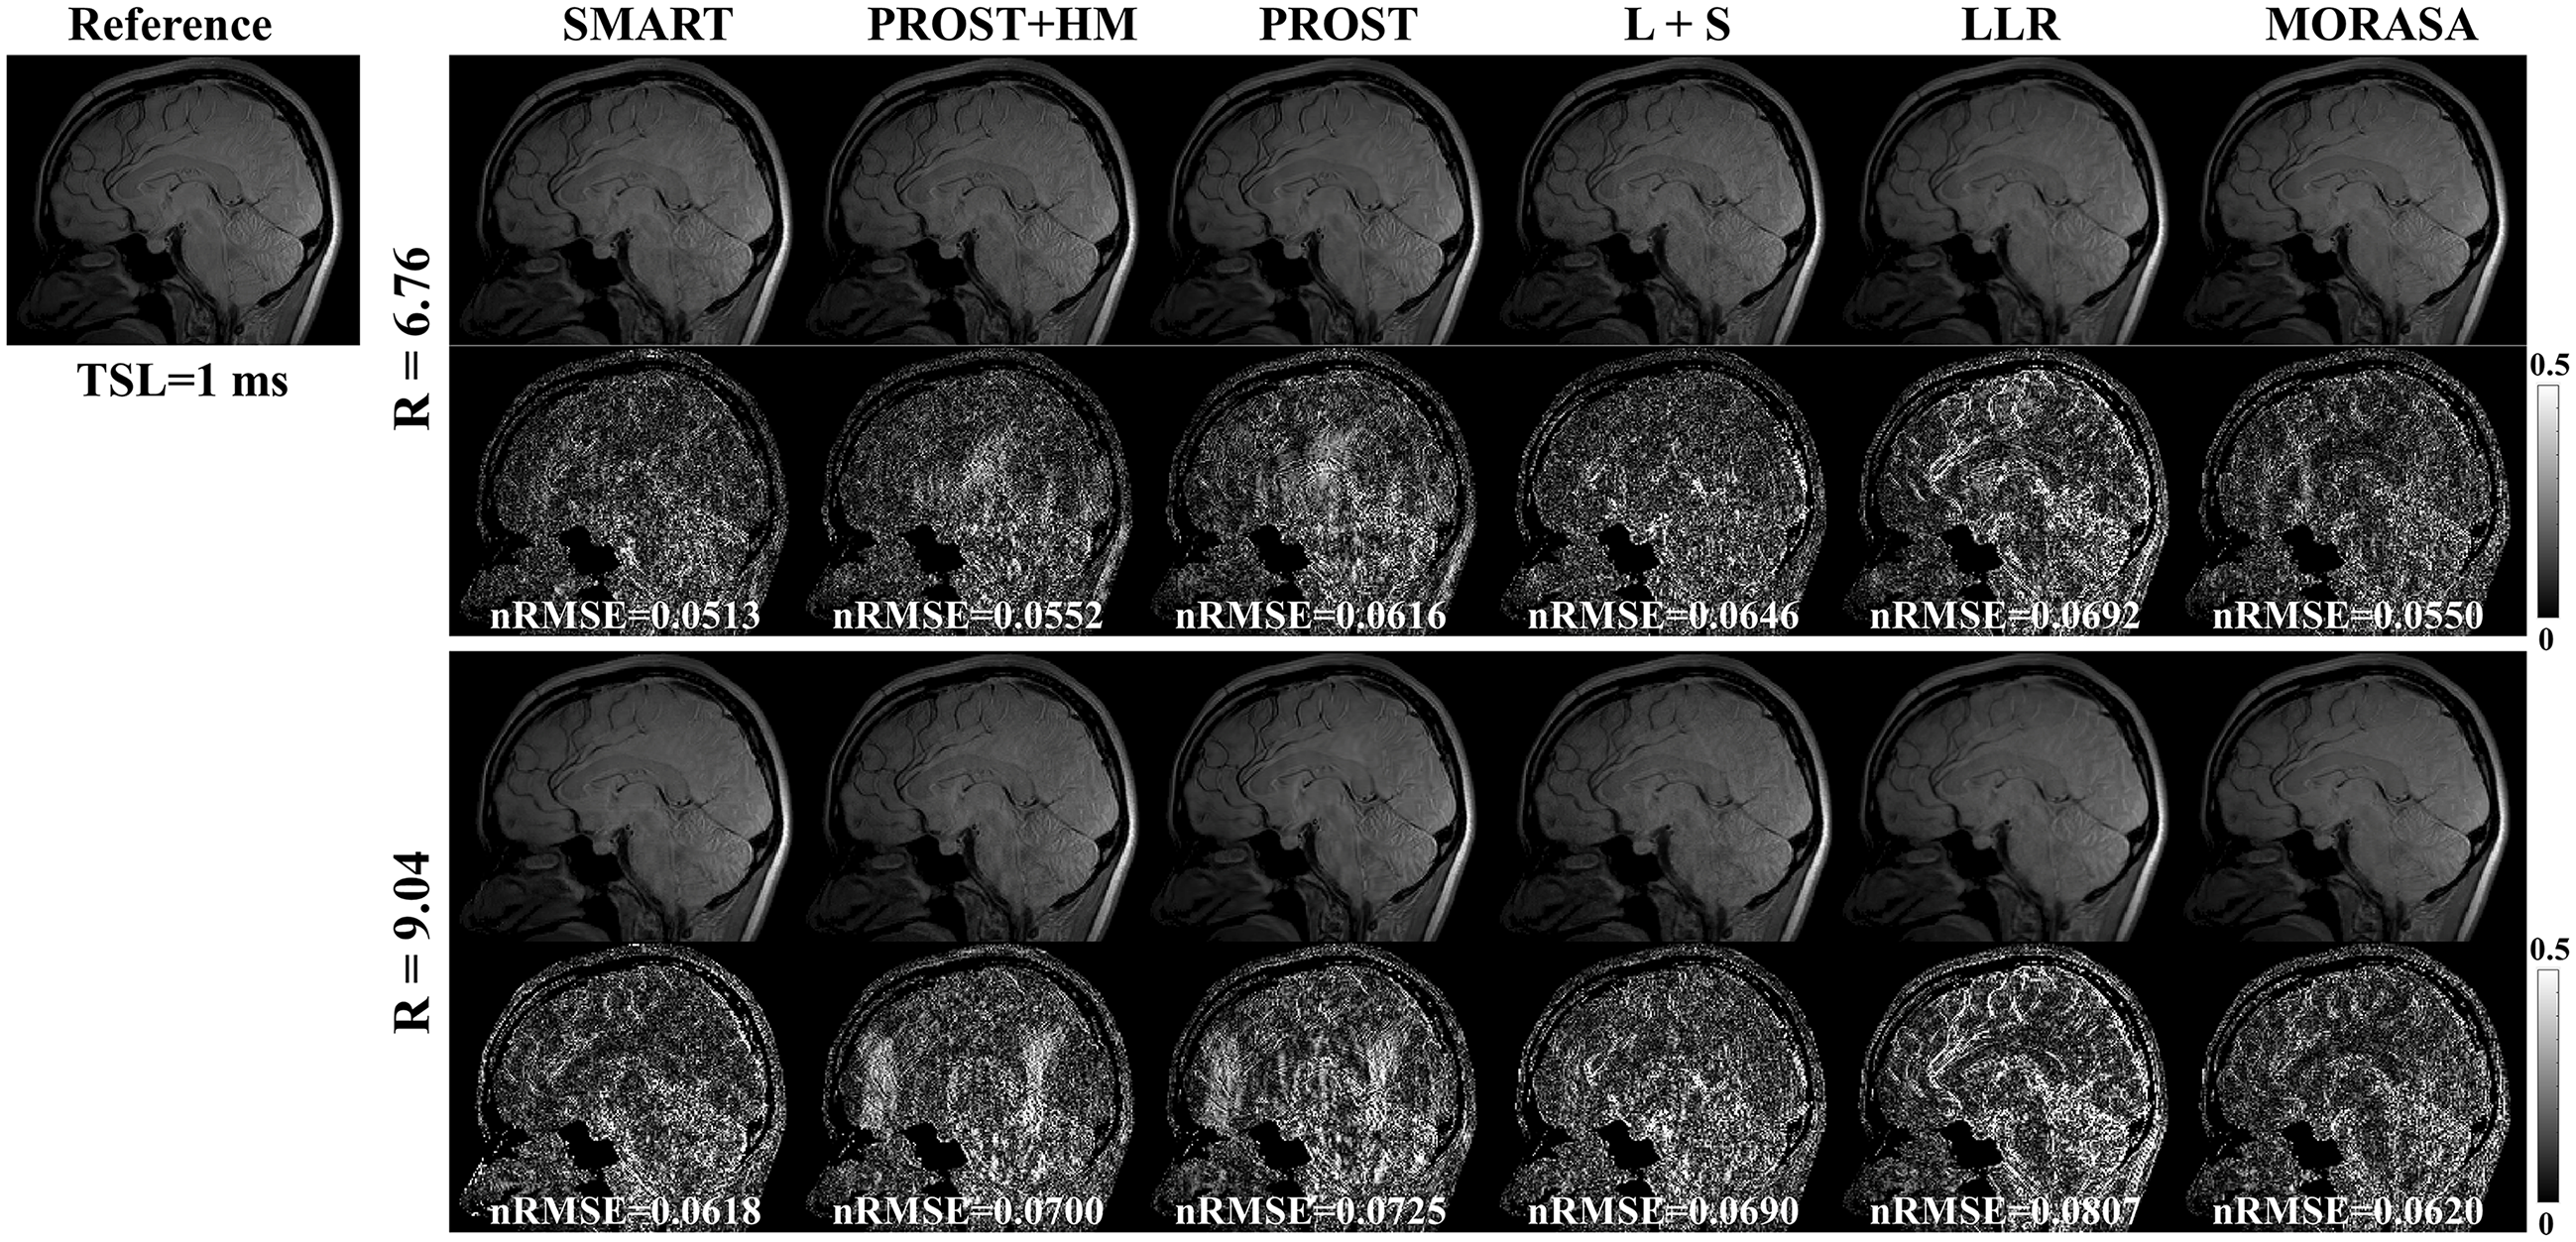

4.4.1 Low acceleration with 6.76-Fold and 9.04-Fold

The -weighted images (at TSL = 1 ms) from one slice of the reconstructed 3D images using the SMART, PROST + HM PROST, L + S, LLR, and MORASA methods for R = 6.76 and 9.04 are shown in Fig.7. The maps reconstructed using the methods above are shown in supplementary information Fig. S5.

4.4.2 Low acceleration with 11.26-Fold and 13.21-Fold

Fig. 8 shows the reconstructed -weighted images and the related error maps at TSL = 1 ms with R = 11.26 and 13.21 using the six methods in 3D imaging. The estimated maps from the reconstructions are shown in supplementary information Fig. S6. At high acceleration, the low-rank tensor-based reconstruction methods (SMART, PROST, and PROST+HM) show better detail retention than the low-rank matrix-based methods (LLR and MORASA). The SMART method still achieves lower nRMSE than other methods at higher accelerations.